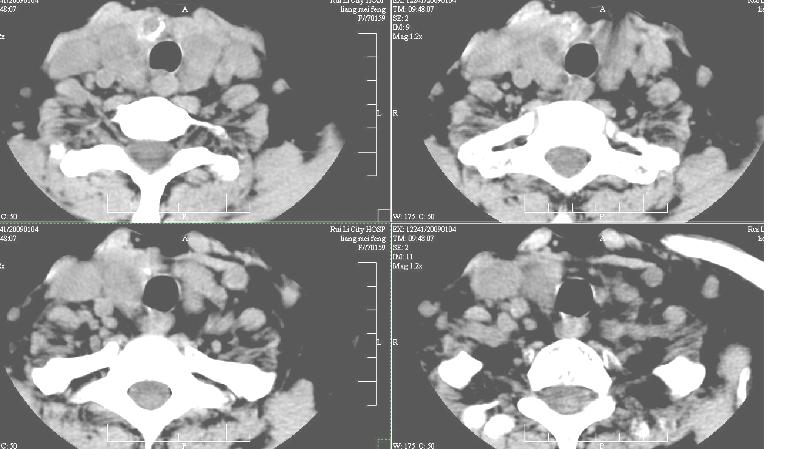

双侧甲状腺稍肿,右侧触及包块,随吞咽上下活动。 1、双侧甲状腺肿(摄碘率降低)。2、右侧甲状腺多发腺瘤,必要时增强。平扫

增强:1、双侧甲状腺肿。2、平扫甲状腺内多发占位病变,增强显示不清楚,境界欠清,请结合临床考虑甲状腺瘤。

右侧甲状腺占位及右侧淋巴结肿大,考虑甲状腺癌!期待结果!